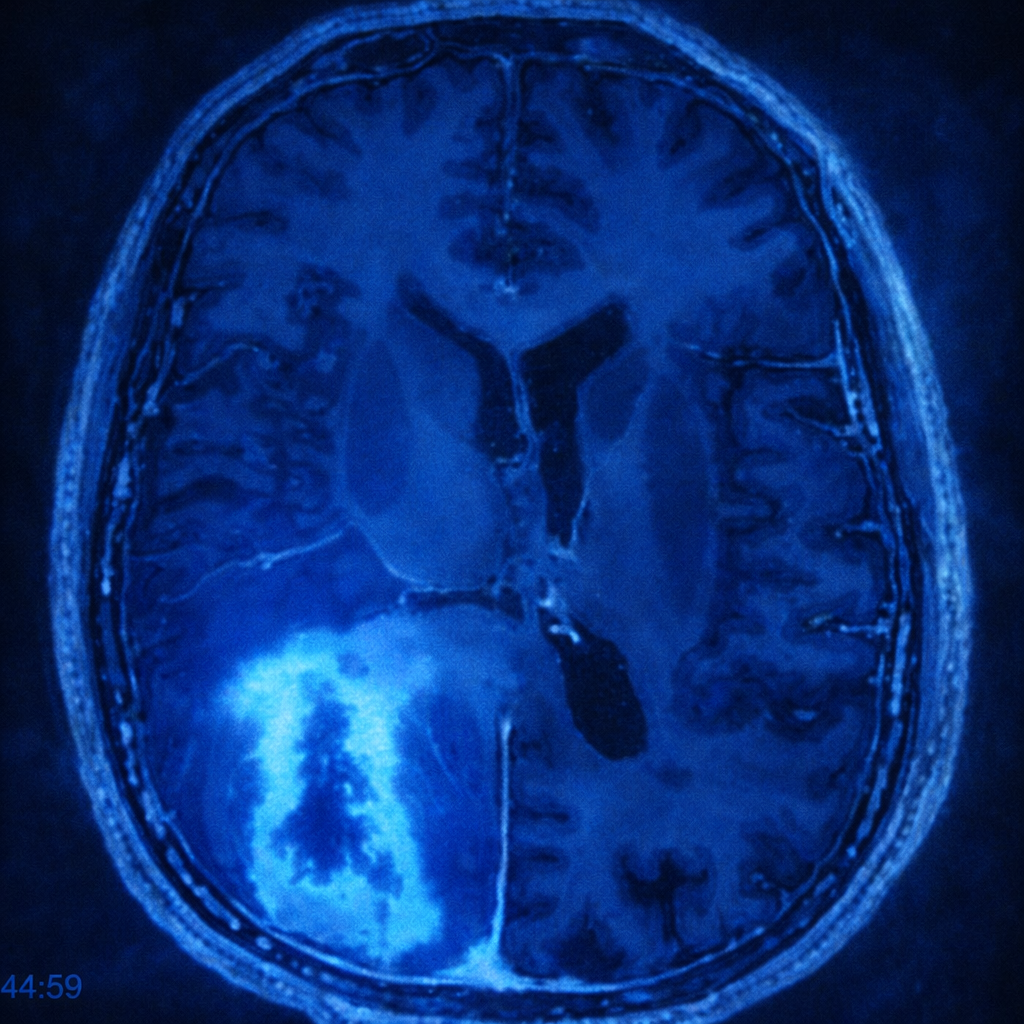

Glioblastoma multiforme (GBM)

Es el tumor cerebral maligno más frecuente y agresivo en adultos. Se origina en las células gliales del cerebro, encargadas de sostener y proteger las neuronas. Este tipo de cáncer se caracteriza por su rápido crecimiento y su capacidad de infiltrarse en el tejido cerebral sano, lo que dificulta su tratamiento. Aunque representa un desafío terapéutico, existen opciones que pueden mejorar la calidad de vida y prolongar la supervivencia.

- Resonancia magnética (RM): principal herramienta para localizar el tumor y evaluar su extensión.